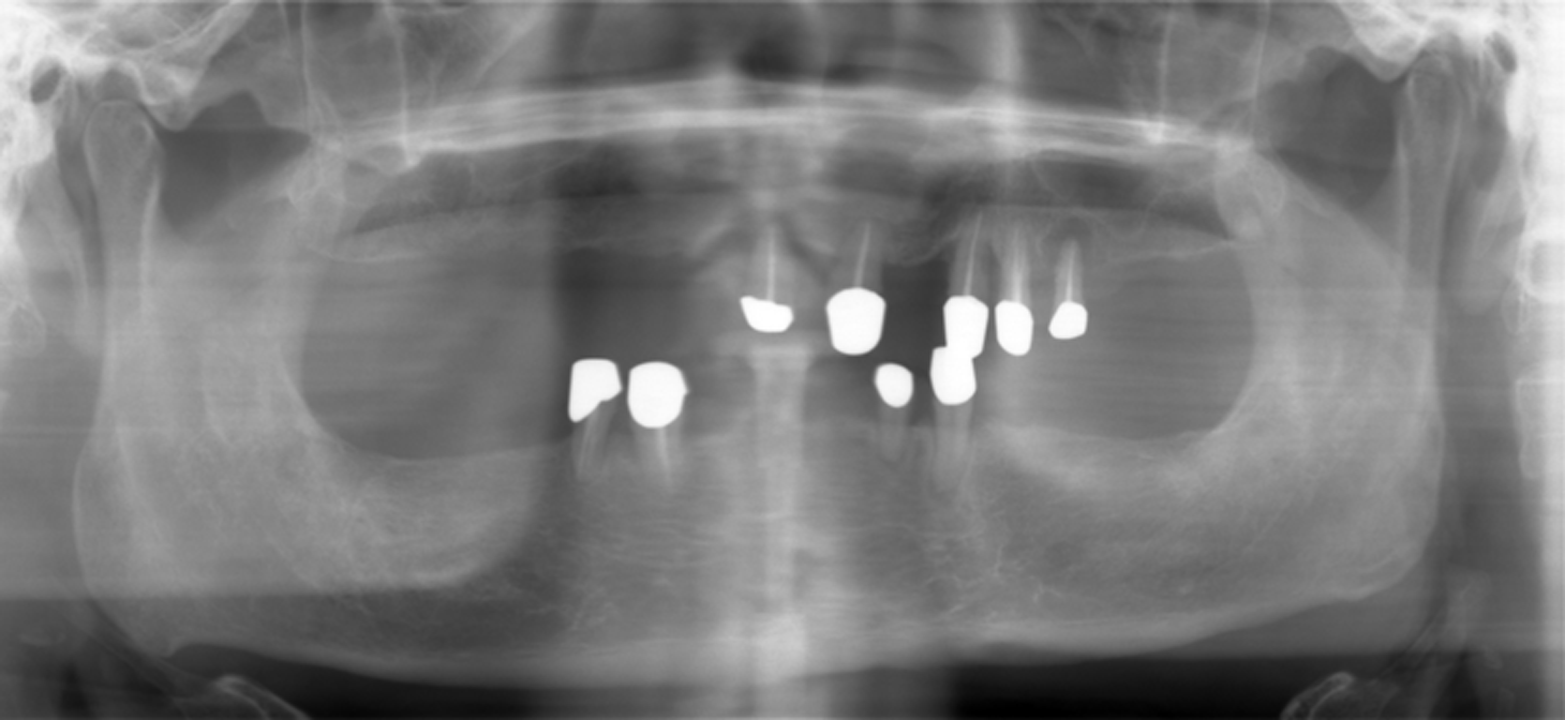

Fig.1 Panoramic X-ray show sufficient bone height in the mandible. Back to main text